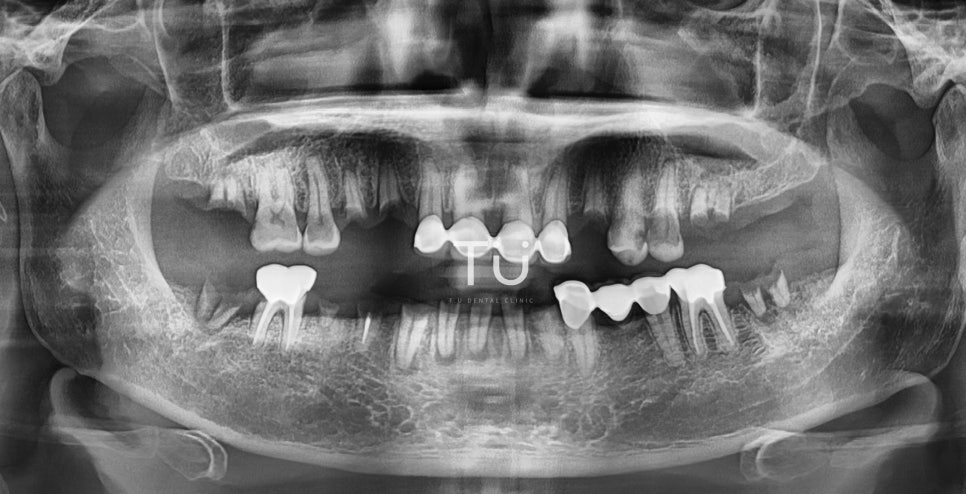

Before

50대 초반 여성 환자분으로,

치아가 많이 상실된 상태에서 내원해주셨습니다.

제대로 음식을 씹는 것도 힘들고,

통증이 있어 무척 괴로워하셨던 환자분입니다.

원래는 하악에 틀니를 착용하셨는데,

식사를 하시다가 아래 틀니가 부러지셨다고 해요.

환자분과 충분한 상담을 진행하였는데,

장기적으로 봤을 때 임플란트로 진행하는 것이

적합하다고 판단되어 치료를 시행하였습니다.